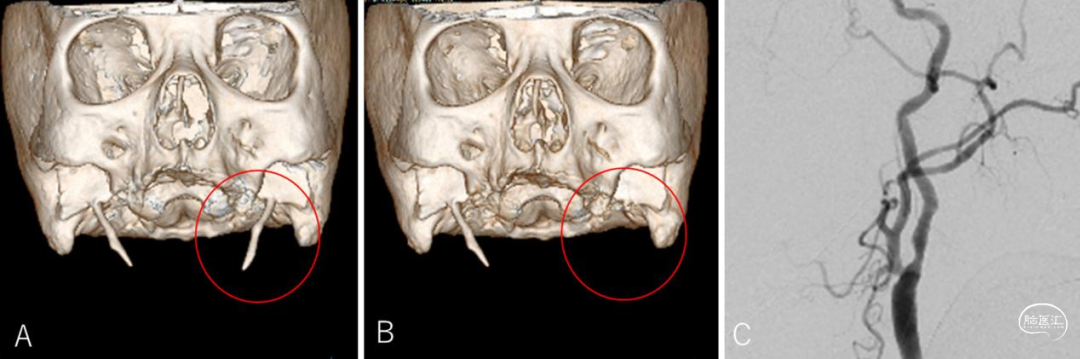

● 标准数字减影血管造影(DSA)显示与磁共振成像(MRI)相似的结果(图2),同样未能揭示病因。鉴于症状由特定头位诱发,提示血管动态受压可能,对其进行了头位变换的DSA检查(手术团队称其为“动态DSA”)。

● Eagle综合征在特定头位下反复出现短暂意识障碍的情况较为罕见。其鉴别诊断包括心脏疾病、神经介导性晕厥、癫痫和猎人弓综合征(Bow hunter’s syndrome,涉及椎动脉)。诊断时,动态DSA具有优势,能够实时观察血流变化并模拟症状发作时的头位,比常规增强CT或MRI更有效。

● 在本病例中,症状仅在特定头位下短暂出现数秒,因此增强CT难以捕捉,而动态DSA则显示出其独特的优势。动态DSA不仅能提高Eagle综合征的诊断率,还能减少辐射暴露和对比剂用量。